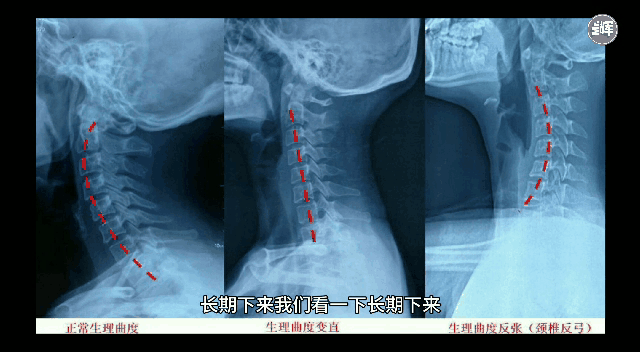

长期下来我们的颈椎曲度会逐渐变小,直至曲度消失,甚至向后反弓。